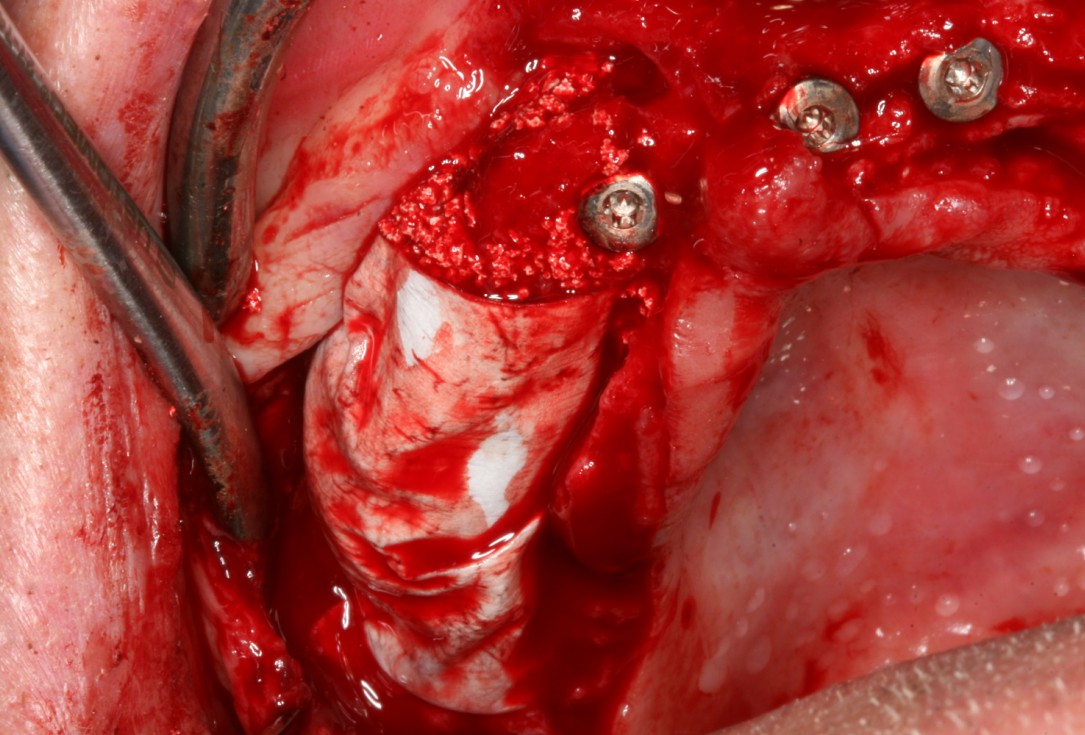

04/10 - Lateral deposition of maxresorb® to prevent resorption of the vestibular wallCircular bone splitting with maxresorb® & collprotect® membrane - PD Dr. J. Neugebauer